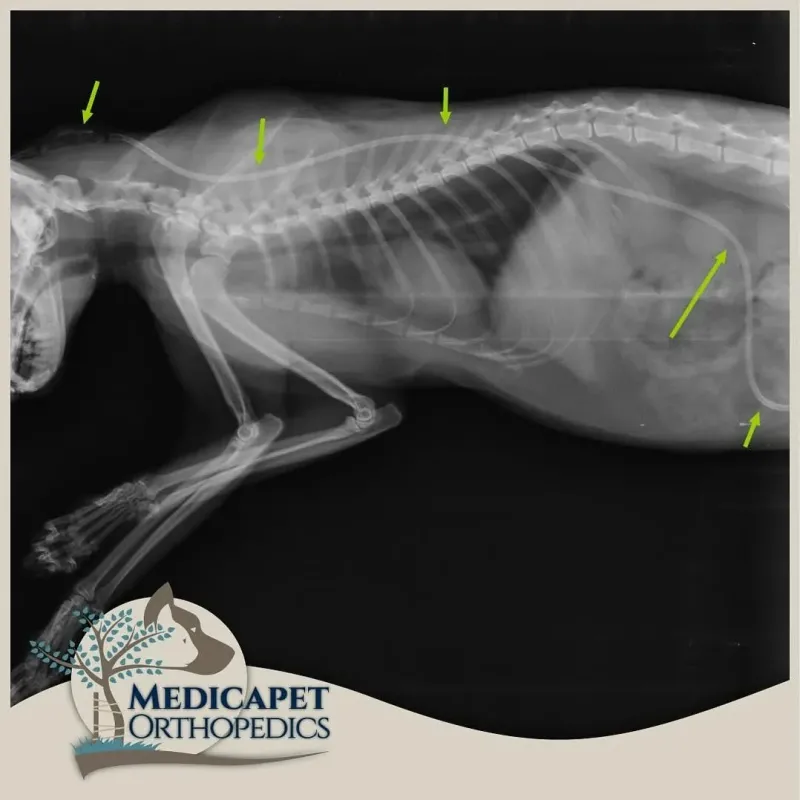

Teşhis

Teşhis seçeneklerinden önce şunun çok iyi bilinmesi gerekir ki: HYDROCEPHALUS’UN ERKEN TEŞHİSİ HAYATİ ÖNEM TAŞIR! PEK ÇOK VAKADA SAATLER BİLE ÖNEMLİDİR. VAKİT GEÇİRİLMEDEN MÜDAHALE EDİLMELİDİR.

Kesin tanı için olmazsa olmazdır. Konuya hakim bir radyolog tarafından değerlendirilmelidir. Ventriküler sistemdeki genişlemeler ve beyin dokusundaki sinyal artışları veya azalışları hakkında güçlü fikirler verir. Cerrahın elini güçlendirir, operatif hakimiyetini yükseltir.

Cerrahi Tedavi

Ventriculoperitoneal Şant uygulamasını kapsar. Ventriküllerde üretilerek sistemik dolaşıma katılamayan ve beyine yüksek derecede basınç uygulayan BOS’un beyinden kalbe ya da karın boşluğuna aktarılmasını sağlayan bir sistemin yerleştirilmesi işlemidir. Yüksek seviyede tecrübe gerektiren bir operasyondur. Beynin içerisine yerleştirilen bir kateter ense kısmında deri altına yerleştirilmiş olan bir vanaya bağlanır. Bu otomatik slikon vana beyin içerisindeki basınç artınca açılarak kendisine bağlı olan diğer katetere fazla BOS sıvısını akıtarak karın boşluğuna ya da kalbe iletilmesini sağlar. Bu bölgelere gönderilen fazla BOS buralardan emilerek sistemik dolaşıma geçer ve vücut dışına atılır. Medicapet rutin olarak bu ameliyatı yapan Türkiye’deki bir kaç merkezden biridir. Hidrosefalinin cerrahi tedavisinde başarı oranımız oldukça yüksektir. Operasyon sonrasındaki iyileşme oranı, hastanın beyin dokusunun almış olduğu hasarın boyutuna ve ne kadarının reversbl olduğuna bağlıdır. erken müdahale edilen hastanın yaşamsal fonksiyonlarının ve yüksek yaşam standardının korunması daha olasıdır.